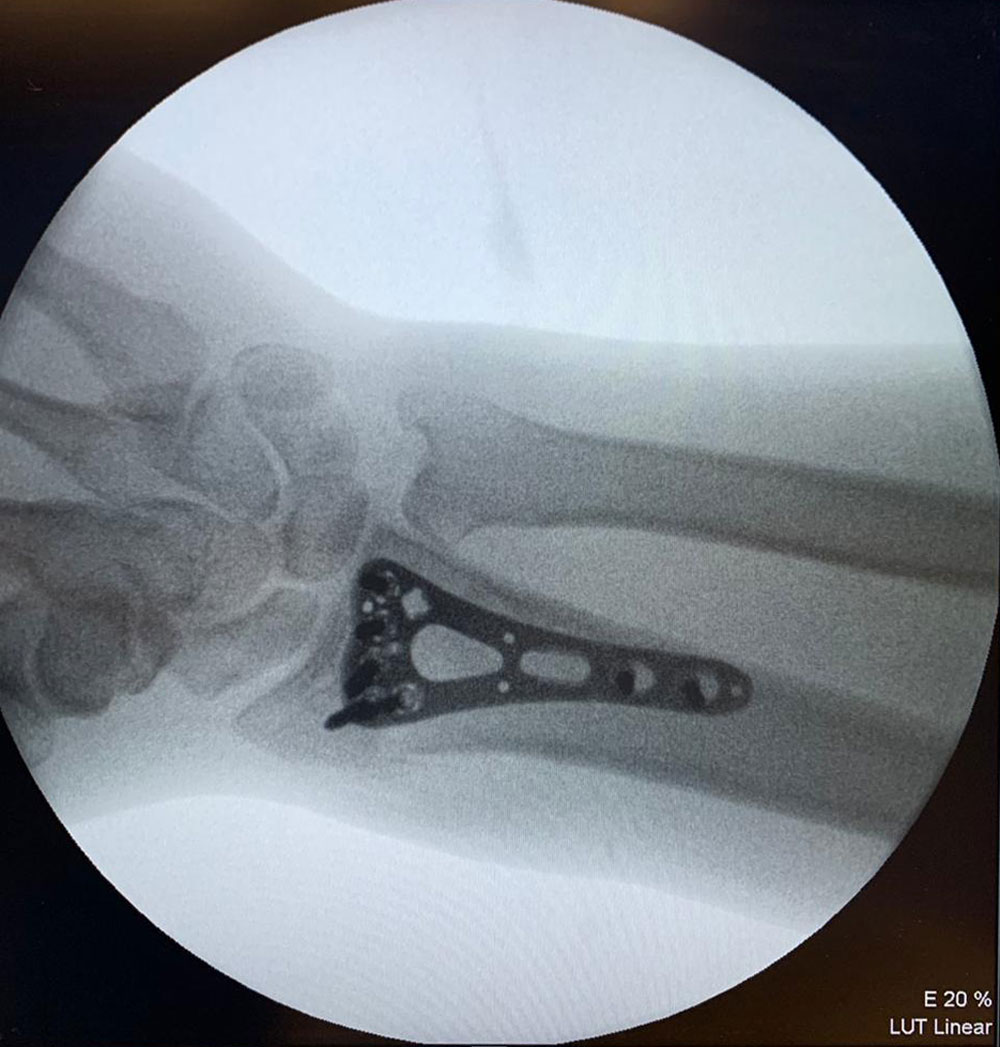

Врачи Пироговского Центра продолжают совершенствовать современные медицинские технологии

Внедрение миниинвазивной хирургии позвоночника

Внедрение методов интраоперационной компьютерной навигации в ортопедии и нейрохирургии

Успешно интегрируется в лечебный процесс технология интраоперационной компьютерной навигации. Стартовав в травматологии и ортопедии, для максимально точного расчета объема вмешательства и прецизионности его выполнения при эндопротезировании суставов, затем в нейрохирургии при выполнении операций на головном и спинном мозге, в настоящее время технология не менее успешно используется в челюстно-лицевой хирургии при коррекции сложных дефектов орбиты, сочетанных травмах и пр. В нашей стране так широко и разнообразно метод применяется только в Пироговском Центре.